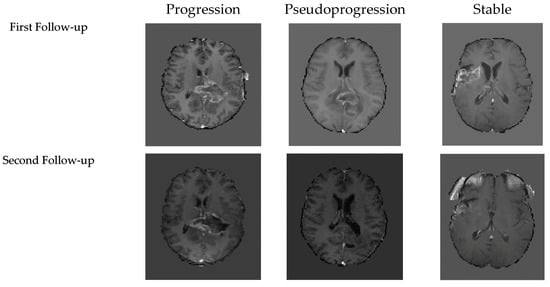

2.2. Labeling Strategy

- Progression override: Any evidence of true progression at any timepoint defined the patient as Progression, irrespective of prior or subsequent labels, given its clinical impact.

- Pseudoprogression: A patient was labeled PsP if the most recent follow-up indicated PsP and no prior imaging confirmed progression. PsP was also retained if the initial PsP was followed by stability or response without subsequent progression.

- Stable disease: Patients with 3 consecutive follow-ups showing only stability or response, without new progression, were labeled Stable.